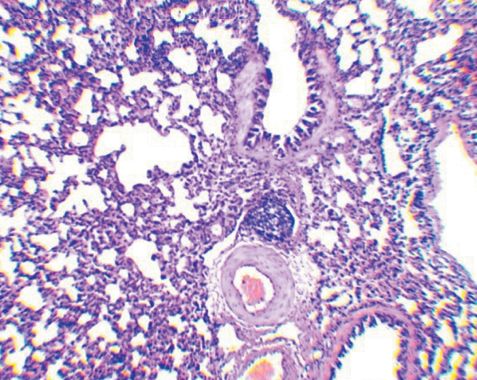

Рис. 1. Легкое морской свинки (группа № 1, контроль) - лимфатические фолликулы с выраженным центром размножения; в нижнем фолликуле отмечается связь с кровеносным сосудом (окраска гематоксилином и эозином, ув. х50) В легких морских свинок, иммунизированных АГ БЦЖ+БК (2-я группа), среди размножающихся в межальвеолярной ткани клеток обнаруживается большое количество плазмоцитов. Пролиферация лимфоидных клеток вокруг кровеносных сосудов и бронхов с образованием клеточных муфт у морских свинок 2-й группы выражена значительно меньше по сравнению с конт рольной группой. Возле стенок бронхов разного калибра скопление лимфоидных клеток либо отсутствует, либо оно незначительно. Вокруг большинства кровеносных сосудов также отсутствуют муфты из лимфоидных клеток, а если они есть, то также имеют небольшую ширину. Формирования фолликулов в периваскулярных муфтах не выявлено. Количество лимфатических фолликулов в легких морских свинок, сенсибилизированных АГ БЦЖ+БК визуально меньше относительно группы №1 (рисунок 2). В фолликулах не выражена зона размножения (рисунок 3).

Рис. 2. Легкое морской свинки (группа № 2) - участки уплотнения разного размера в ткани легкого; лимфатический фолликул около бронха и кровеносного сосуда (окраска гематоксилином и эозином, ув. х50)  Рис. 3. Легкое морской свинки (группа № 2) - лимфатический фолликул без зоны размножения, формирующийся около сосуда (окраска гематоксилином и эозином, ув. Х100) У особей, вакцинированных БЦЖ, по сравнению группой № 1 (контроль) размножение эпителиоидных макрофагов в межальвеолярной ткани, а также скопление лимфоидной ткани возле бронхов, сосудов и в форме фолликулов в значительно меньшей степени выражено. Лимфоидные клетки образуют вдоль бронхов небольшого размера скопления. Периваскулярные муфты из лимфоидных клеток имеют небольшую ширину и протяженность, в них не наблюдается выраженный процесс формирования лимфатических фолликулов, но в сформировавшихся фолликулах сохраняется связь с кровеносными сосудами. В лимфатических фолликулах, в отличие от контрольной группы генеративные и реактивные центры не выражены. Меньший размер лимфатических фолликулов у морских свинок 2-й и 3-й опытной группе также подтверждается морфометрическими исследованиями, результаты которых представлены в таблице 1. Таблица 1 Морфометрические показатели лимфатических фолликулов BALT у морских свинок, инфицированных M. bovis, после введения противотуберкулезных препаратов, M±m | № группы (препарат) | Средний диаметр (мкм) | Средний радиус(мкм) | Средняя площадь (мкм2) | % | | №1 (контроль) | 203,0±8,8 | 101,5±4,4 | 34103,0±2766,5 | 89,0 | | №2 (конъюгат антигенов БЦЖ с бетулоновой кислотой) | 115,7±6,5** | 57,8±3,2** | 11458,4±1240,7** | 10,2 | | №3 (вакцина БЦЖ) | 155,0±9,1** | 77,2±4,4* | 20742,3±2386,4* | 0,4 | | Свиньи | 8 | 0,5 | 49 | 0,3 | | Всего: | 1590 | | 18976 | | Примечание: * - p<0,01; ** - p<0,001 Морфометрические исследования показали, что лимфатические фолликулы инфицированных морских свинок контрольной группы имеют диаметр 203,0±8,8 мкм, радиус 101,5±4,4 мкм и площадь 34103,0±2766,5 мкм2 (табл. 1). При инокуляции экспериментального конъюгата средний диаметр, радиус и площадь фолликулов в легких составили соответственно 115,7±6,5 мкм, 57,8±3,2 мкм и 11458,4±1240,7 мкм2 и были по сравнению с морскими свинками контрольной группы значительно меньшими, о чем свидетельствовало достоверное снижение указанных показателей в 1,75-2,97 раза. У морских свинок, иммунизированных вакциной БЦЖ, также в значительной степени отличались от контрольной группы, на что указывало достоверное уменьшение анализируемых морфометрических параметров в 1,31 - 1,64 раза. Эти показатели были выше, чем в группе особей, подвергнутых обработке экспериментальным конъюгатом. При гистологическом исследовании легких морских свинок, инфицированных вирулентным штаммом микобактерий, установлено, что формирующийся иммунный ответ на генерализацию возбудителя сопровождается размножением лимфоидных клеток вокруг кровеносных сосудов и бронхов разного калибра и образованием типичных лимфатических фолликулов. Преимущественное обнаружение лимфоидной ткани в виде клеточных муфт различной ширины и длины вокруг кровеносных сосудов указывает на гематогенную диссеминацию возбудителя. Разрастаясь эксцентрично, лимфоидные муфты, локализующиеся вокруг кровеносных сосудов, формируют множество фолликулов с центрами размножения и реактивными центрами, которые, по нашему мнению, относятся к iBALT, являющейся свидетельством антигенной стимуляции, вызванной наличием в крови возбудителя. Ряд исследователей отмечает, что фолликулы в реактивных областях iBALT могут содержать крупные зародышевые центры, в которых В-клетки быстро размножаются в ответ на воздействие антигена [5]. Т-клеточная зона iBALT, содержащая Т-хелперы, Т-супрессоры и обычные дендритные клетки, окружает В-клеточные фолликулы [10]. Отсутствие туберкул с активным процессом в легких зараженных морских свинок может быть результатом действия iBALT. Так, T. Ulrichs et al. [11] в своем исследовании указывает, что развитие таких лимфоидных скоплений в легких было связано с контролируемым туберкулезным процессом, тогда как отсутствие или дезорганизация iBALT - с неконтролируемой инфекцией M. tuberculosis. После применения противотуберкулезных препаратов обнаруживалось существенно меньшее, чем у не иммунизированных морских свинок, количество лимфоидной ткани вокруг сосудов и бронхов. Значительно меньшим был и диаметр фолликулов, в которых не были явно выражены центры размножения, а реактивных центров выявлено не было. Связано это, по нашему мнению, с уменьшением концентрации антигена в крови в результате выработки иммунитета. В ряде работ также указывается на выработку при вакцинации БЦЖ иммунитета в легких, приводящего к уменьшению роста микобактерий [12]. Заключение. На основании проведенных исследований можно прийти к заключению о том, что инокуляция экспериментального конъюгата индуцирует существенное снижение реакции бронхоассоциированной лимфоидной ткани, которое выражается в уменьшении среднего диаметра, радиуса и площади лимфатических фолликулов и их активности. Вместе с тем, в ткани легких морских свинок, подвергнутых обработке экспериментальным конъюгатом, визуально регистрировалось большее количество плазматических клеток, что может указывать на стимуляцию гуморального звена иммунитета, индуцированную действием этого препарата. Список литературы: 1. He W., Zhang W., Cheng C., Li J., Wu X., Li M., Chen Z., Wang W. The distributive and structural characteristics of bronchus-associated lymphoid tissue (BALT) in Bactrian camels (Camelus bactrianus). PeerJ. 2019. Vol. 7. e6571. 2. Silva-Sanchez A., Randall T.D. Anatomical Uniqueness of the Mucosal Immune System (GALT, NALT, iBALT) for the Induction and Regulation of Mucosal Immunity and Tolerance. Mucosal Vaccines. 2020. P. 21-54. 3. Seefeld M.L., Templeton E.L., Lehtinen J.M., Sinclair N., Yadav D., Hartwell B.L. Harnessing the potential of the NALT and BALT as targets for immunomodulation using engineering strategies to enhance mucosal uptake. Front. Immunol. 2024. Vol.15. P. 1419527. 4. Marin N.D., Dunlap M.D., Kaushal D., Khader S.A. Friend or Foe: The Protective and Pathological Roles of Inducible Bronchus-Associated Lymphoid Tissue in Pulmonary Diseases // J Immunol. 2019. Vol. 202(9): 2519-2526. doi: 10.4049/jimmunol.1801135 5. Hwang J.Y., Randall T.D., Silva-Sanchez A. Inducible Bronchus-Associated Lymphoid Tissue: Taming Inflammation in the Lung. Front Immunol. 2016. Vol. 7: 258. 6. Dunlap M.D., Prince O.A., Rangel-Moreno J., Thomas K.A., Scordo J.M., Torrelles J.B., Cox J., Steyn A.J.C., Zuniga J., Kaushal D., Khader S.A. Formation of Lung Inducible Bronchus Associated Lymphoid Tissue Is Regulated by Mycobacterium tuberculosis Expressed Determinants. Front Immunol. 2020. Vol. 11. P. 1325. 7. Bachvarova M., Stefanova T., Nikolaeva S., Chouchkova M. Tuberculin sensitivity and morphological immune response in guinea pigs after application of minimal sensitizing dose of BCG vaccine, substrain Sofia SL222. Int Immunopharmacol. 2009. 9 (7-8). P. 1010-1015. 8. Кошкин И.Н., Власенко В.С., Бажин М.А. Функциональная активность нейтрофилов у морских свинок, иммунизированных конъюгатами на основе антигенов БЦЖ с бетулином и его производными. Вестник КрасГАУ. 2021. 5. P. 116-121. 9. Koshkin I.N., Vlasenko V.S., Kulakov I.V. The Effect of Experimental BCG Antigen-Betulin-Derived Conjugates on the Guinea Pig Immunological Response. Russ J Bioorg Chem. 2021. Vol. 47. P. 837-844. 10. Vinuesa C.G., Linterman M.A., Yu D., MacLennan I.C. Follicular helper T cells. Annu Rev Immunol. 2016. Vol. 34. P. 335-368. 11. Ulrichs T., Kosmiadi G.A., Jorg S., Pradl L., Titukhina M., Mishenko V., Gushina N., Kaufmann S.H. Differential organization of the local immune response in patients with active cavitary tuberculosis or with nonprogressive tuberculoma. J Infect Dis. 2005. Vol. 192(1). P. 89-97. 12. Ordway D., Henao-Tamayo M., Shanley C., Smith E.E., Palanisamy G. Influence of Mycobacterium bovis BCG Vaccination on Cellular Immune Response of Guinea Pigs Challenged with Mycobacterium tuberculosis. Clin Vaccine Immunol. 2008. Vol. 15 (8). P. 1248-1258. Сведения об авторах: Кошкин Иван Николаевич, кандидат ветеринарных наук, старший научный сотрудник лаборатории эпизоотологии и мер борьбы с туберкулезом ФГБНУ «Омский аграрный научный центр»; 644001 Омская область, г. Омск, ул. Лермонтова, д. 93; тел.: 8-929-3656869; e-mail: koshkin@anc55.ru. Ответственный за переписку с редакцией: Власенко Василий Сергеевич, доктор биологических наук, профессор, главный научный сотрудник лаборатории эпизоотологии и мер борьбы с туберкулезом ФГБНУ «Омский аграрный научный центр»; 644001 Омская область, г. Омск, ул. Лермонтова, д. 93; тел.: 8-951-4083421; e-mail: vvs-76@list.ru. Заявленный вклад авторов: Кошкин И. Н.: формальный анализ, проведение исследования, визуализация, написание черновика рукописи. Власенко В. С.: разработка концепции, административное руководство исследовательским проектом, валидация результатов, написание рукописи - рецензирование и редактирование. Конфликт интересов: авторы заявляют об отсутствии конфликта интересов.